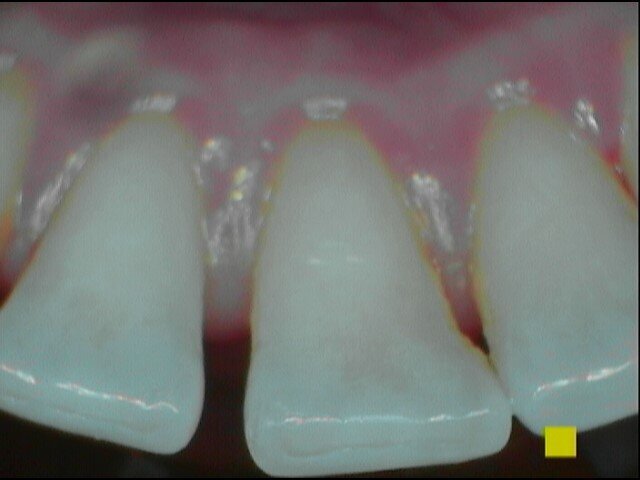

Verifichiamo che il protocollo Tailored Brushing Method (TBM), basato sulla scelta concordata di delle tecnologie più opportune per l’efficacia del controllo del biofilm batterico, è risultato agevole e ha portato esito positivo con indice di placca migliorato e sanguinamento assente. Il paziente ha apprezzato il massaggio gengivale procurato dallo scovolino in silicone che ha accelerato il processo di guarigione della lieve infiammazione a livello interprossimale. È stato eseguito il deplaquing delle superfici dentali con polishing selettivo con l’ausilio di gommini e paste abrasive di diverse granulometrie (Figg. 10-13).

Per il mantenimento del sorriso luminoso, abbiamo consigliato di implementare la seduta di igiene con uno sbiancamento a base di aloe vera (moro white smile). Al controllo il paziente riferisce assenza di percezione di odori sgradevoli nel cavo orale e sul dispositivo invisibile con sensazione di freschezza dopo l’utilizzo del collutorio e di aver spazzolato e igienizzato la mascherina ortodontica con frequenza .Gli indici clinici sono PI pari al 10%, BoP negativo, PDD medio fisiologico (Figg. 14-16).